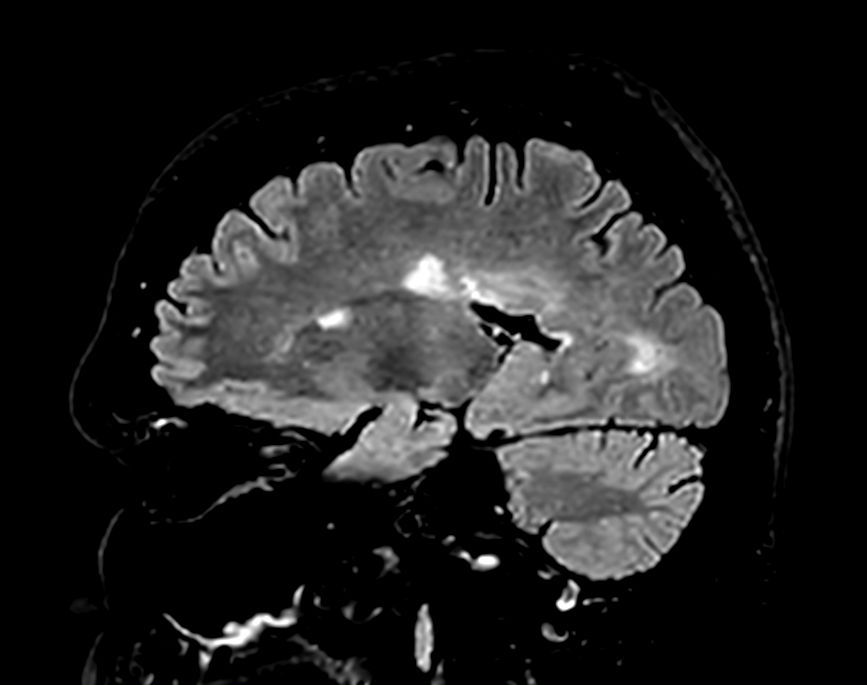

Sagittal 3D FLAIR